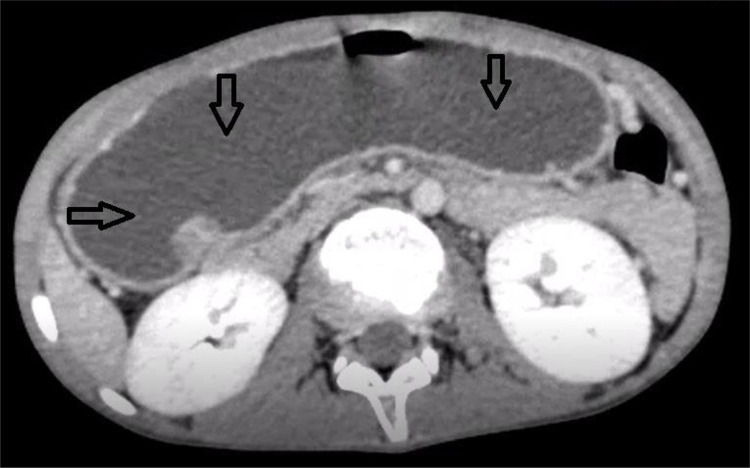

Case presentation: We report the case of a 13-year-old boy with a three-year history of recurrent non-bilious projectile vomiting and epigastric pain. Despite normal laboratory findings, plain computed tomography (CT) and post-intravenous (IV) contrast CT scans revealed features suggestive of gastric outlet obstruction, including significant stomach distention and abrupt tapering of the duodenum. Owing to the inconclusive imaging results, surgical exploration was pursued. Intraoperative findings confirmed the presence of a band of pancreatic tissue encircling the first part of the duodenum, thereby establishing the diagnosis of an annular pancreas. A gastroduodenostomy was successfully performed, resulting in an uneventful recovery and resolution of symptoms during subsequent follow-up.